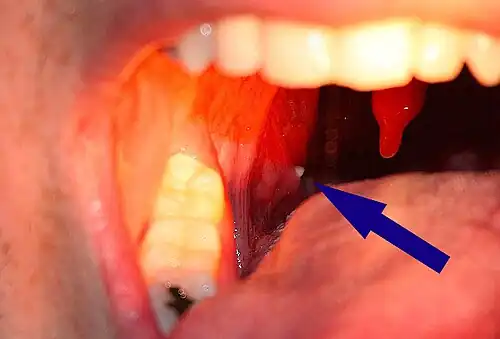

| A tonsillolith lodged in the tonsillar crypt | |

A tonsillolith protrudes from the tonsil -